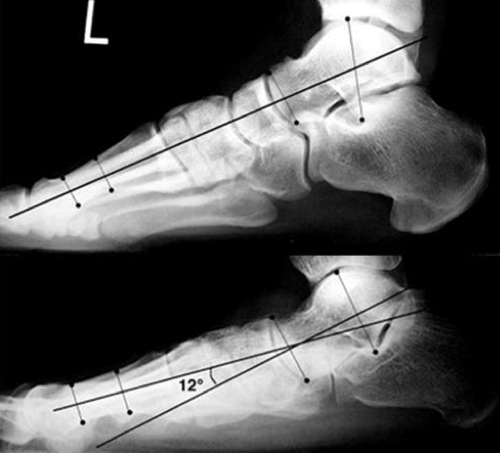

Diagnosis on bottom picture

Pes planovalgus

Meary’s angle is apex plantar

Normal is 0 ± 4 degrees

What measurement is this?

Which pic is abnormal?

Mearys angle

(angle subtended from a line drawn through axis of the talus and axis of 1st ray)

Bottom is abnormal - apex plantar therefore flatfoot